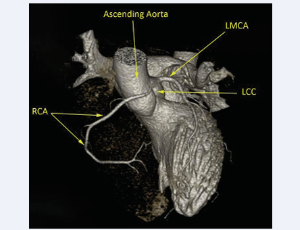

AbstractRobotic-assisted coronary artery bypass graft surgery is an emerging approach since it has been associated with less post-operative complications, and shorter length of stay when compared to conventional surgery. Its utilization is growing up especia.....